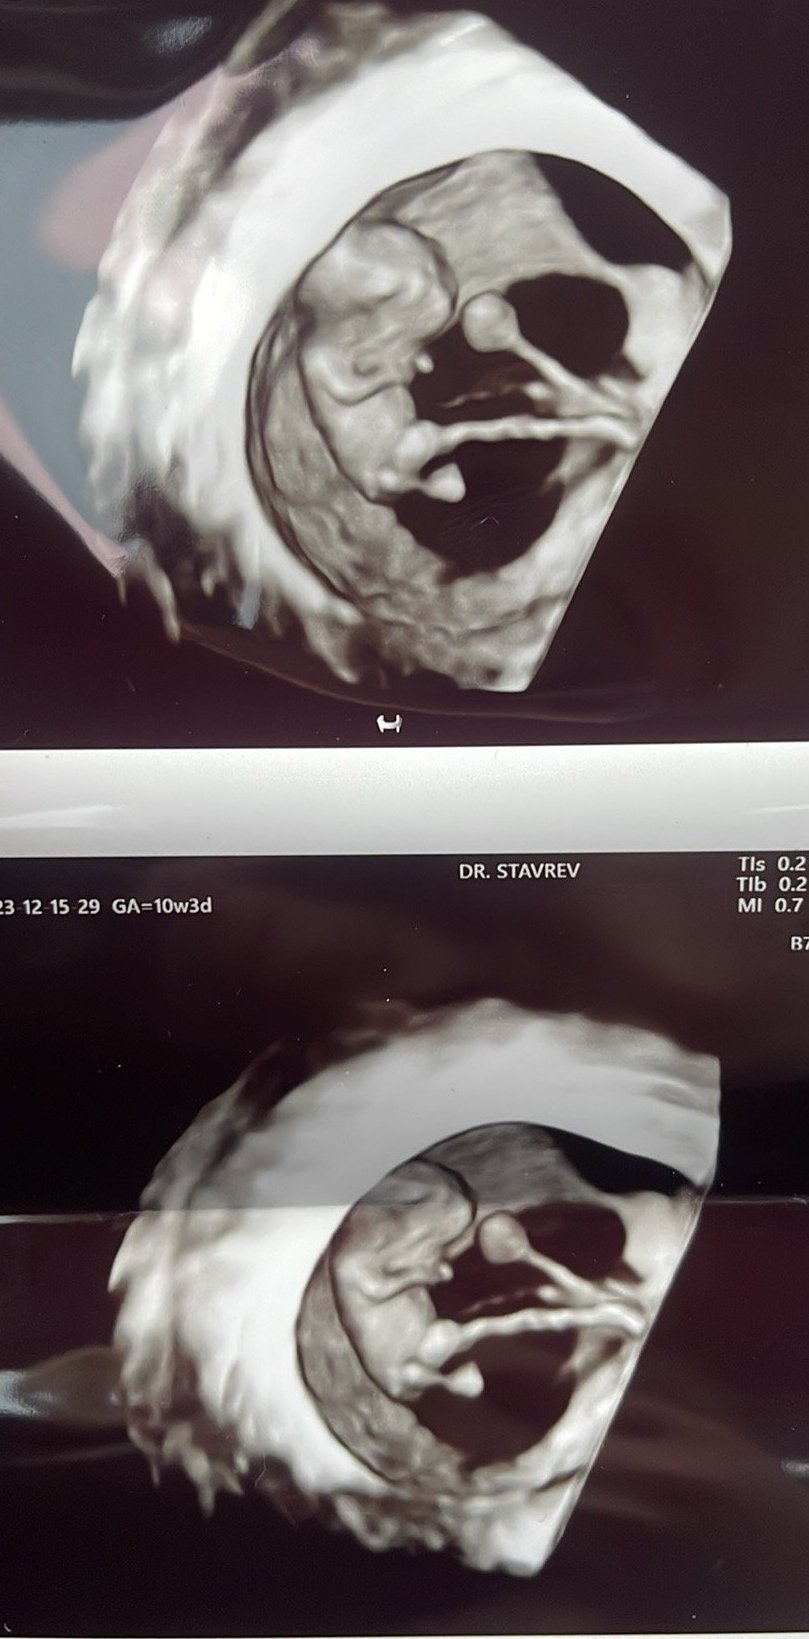

Здравейте, мами! И аз се включвам в темата с термин 14.07.2024 в момента съм в 10г.с. първа бременност на 21г след година опити. Преди няколко дни бях на преглед и направиха малко снимки таа да се похваля...Grinning